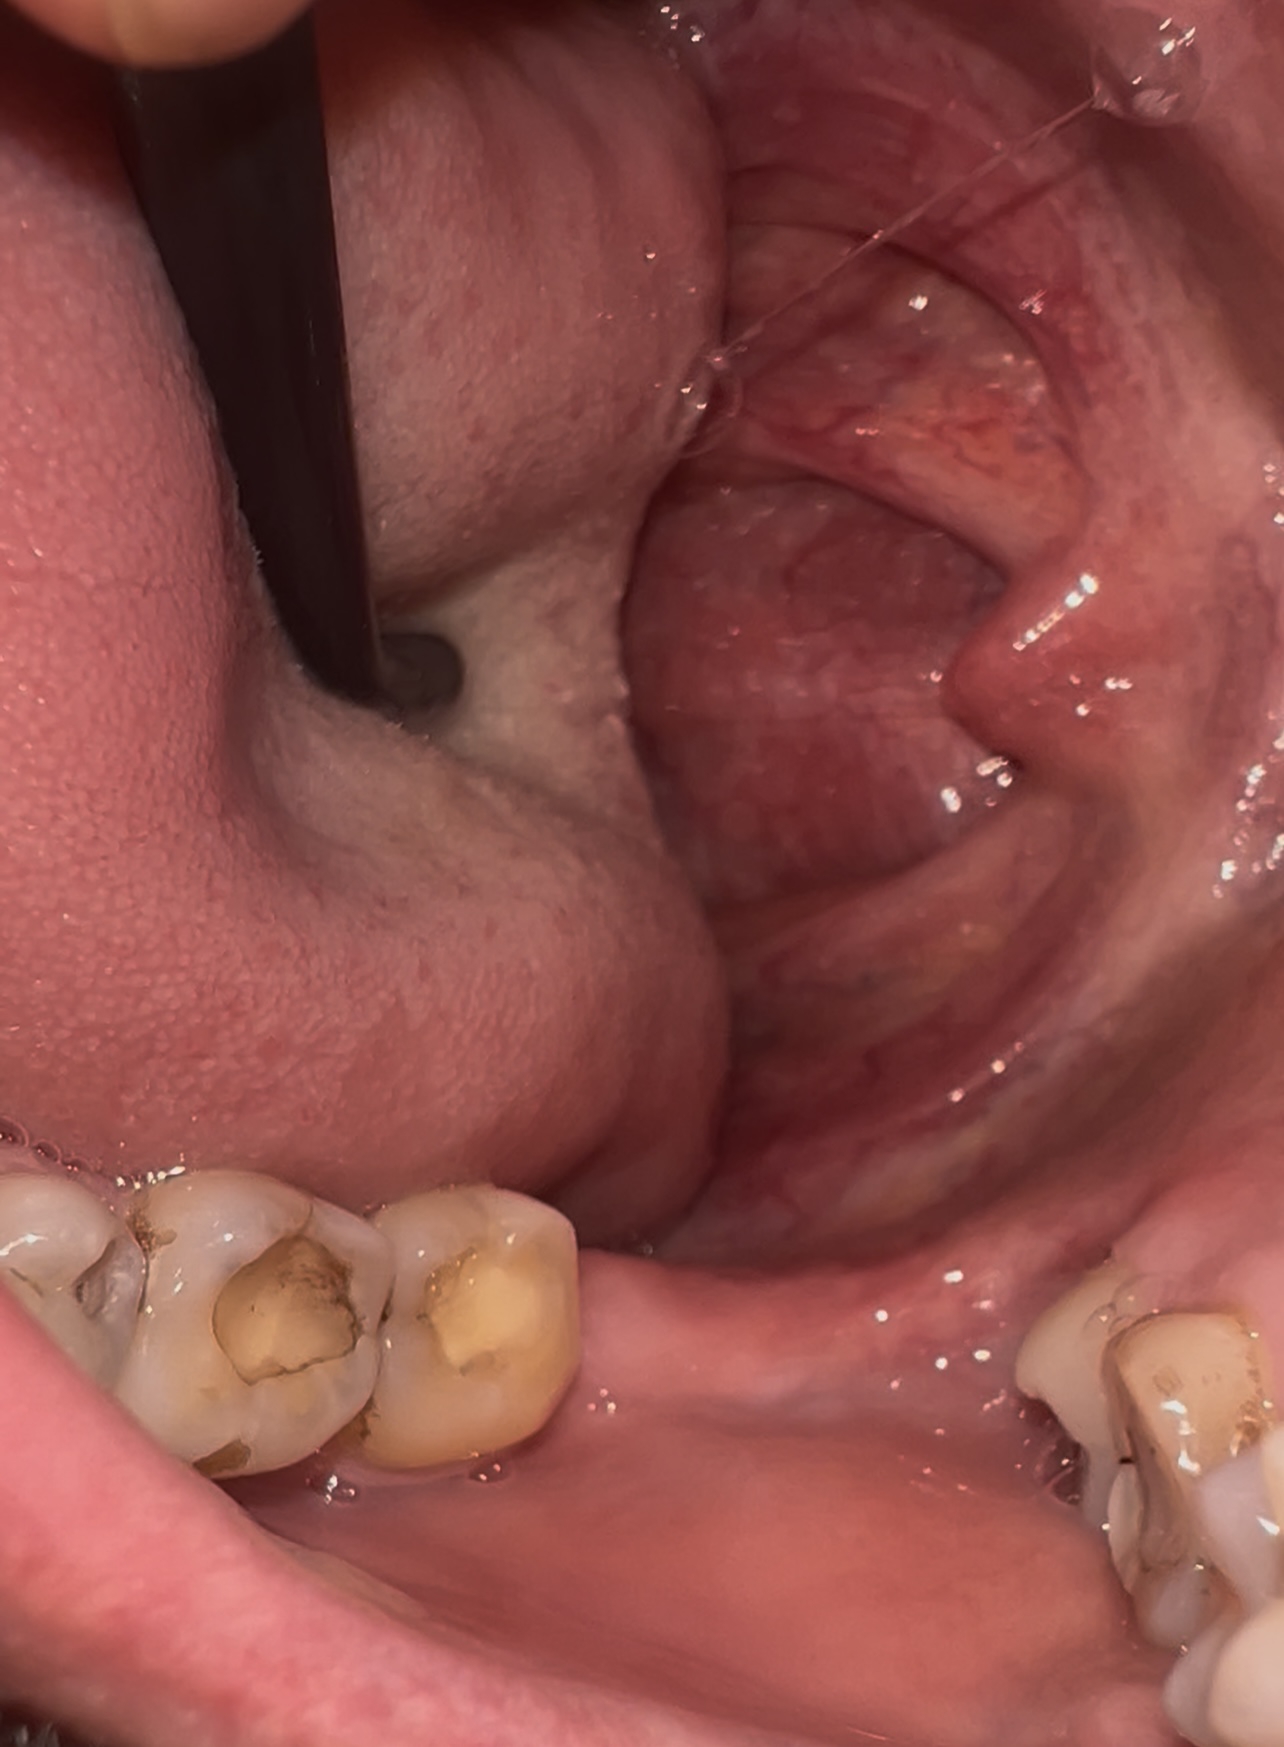

Аноним 10/08/25 Вск 18:26:58 1635518 35

1000070960.jpg 313Кб, 1117x832

1117x832